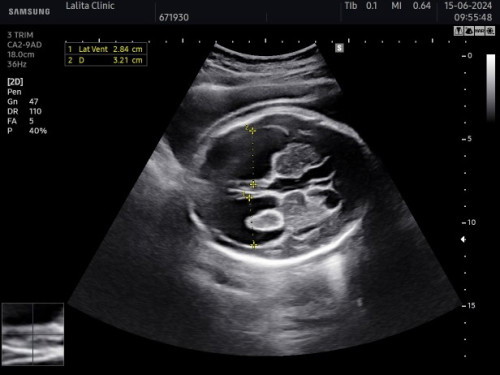

ใครเคยมีประสบการณ์ลูกเป็นโรคโพรงสมองคั่งน้ำบ้างค่ะพอดีตั้งครรภ์ได้8เดือนเพิ่งมาตรวจเจอ